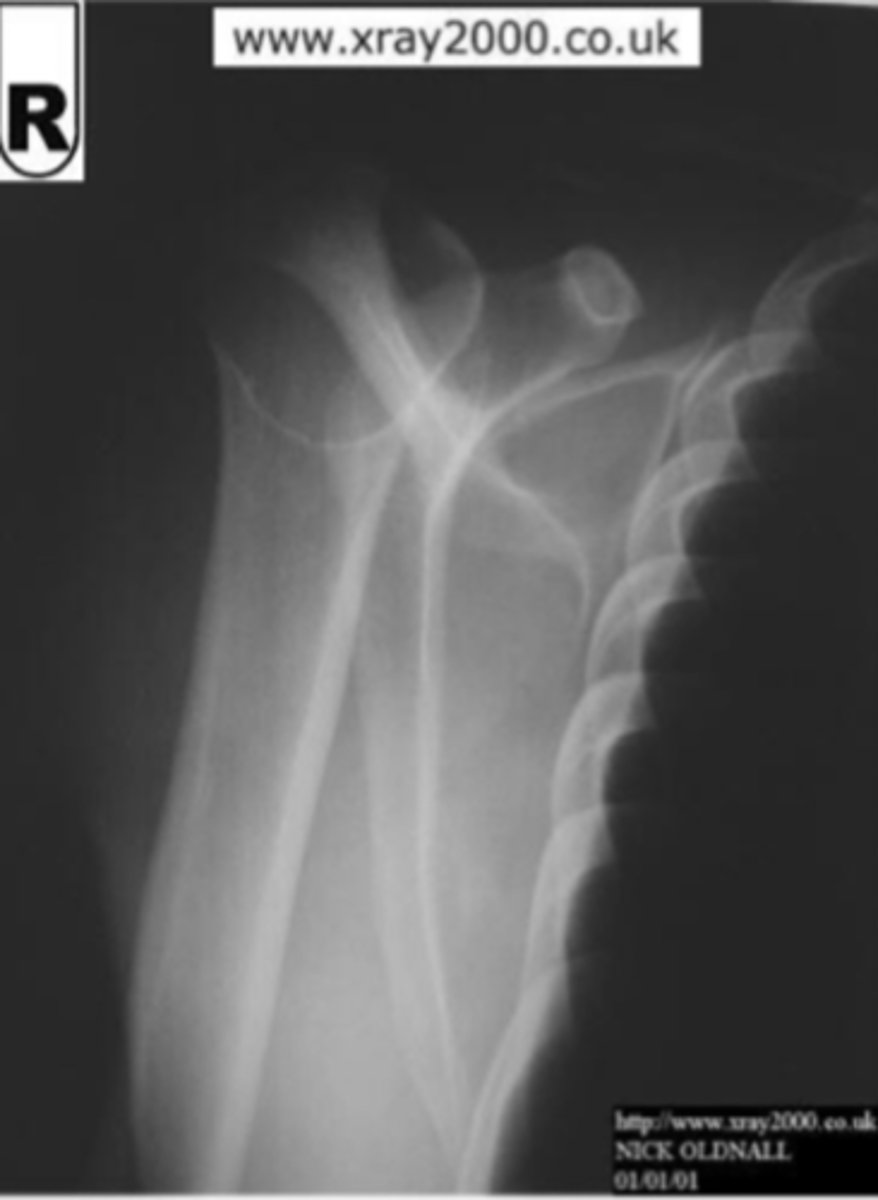

Scaphoid fracture and minor ulnar fracture

What is the issue?

Scaphoid fracture